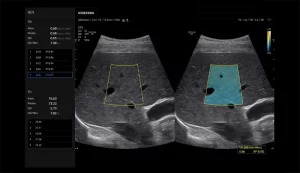

QUS (TAI™/TSI™)

S-Detect™ for Breast

S-Fusion ( برای شکم و پروستات )